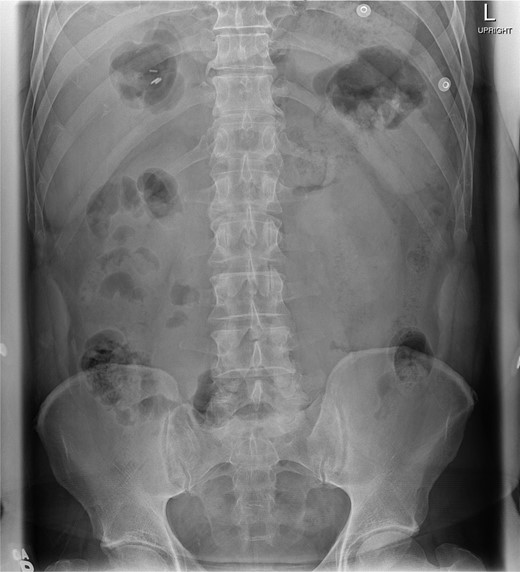

At presentation, his vitals were normal. Abdominal examination revealed an overweight gentleman with focal tenderness to the left upper quadrant. Laboratory tests revealed a WBC of 25.3 with neutrophils of 23.4. Hemoglobin, platelets, electrolytes and liver enzymes were within normal limits. Three views of the abdomen revealed no gross intra-abdominal pathology and no free air was reported on chest X-ray (Figs 1 and 2).

Chest X-ray showing left lower lobe opacity with a small volume of subdiaphragmatic free air.

A CT scan demonstrated significant soft tissue stranding/edema of the omentum in the left hemi-abdomen. In addition, there was mild ascites and multiple scattered locules of air (Figs 3–5). No other abnormality of the small or large bowel was identified. He was admitted for observation and broad-spectrum antibiotic therapy was initiated. On post admission day 2, he became diffusely peritonitic, febrile with a temperature of 39.1°C and his oxygen requirements increased to 12 l/min.

Our case demonstrates the diagnostic dilemma that accompanies delayed bowel injuries. Laboratory tests often give nonspecific results that seldom point to a diagnosis [1]. Imaging studies also fail to establish the etiology. Our CT scan failed to demonstrate significant intraperitoneal free air (Figs 3–5). In addition, oral contrast was utilized, but gross extravasation was not identified.